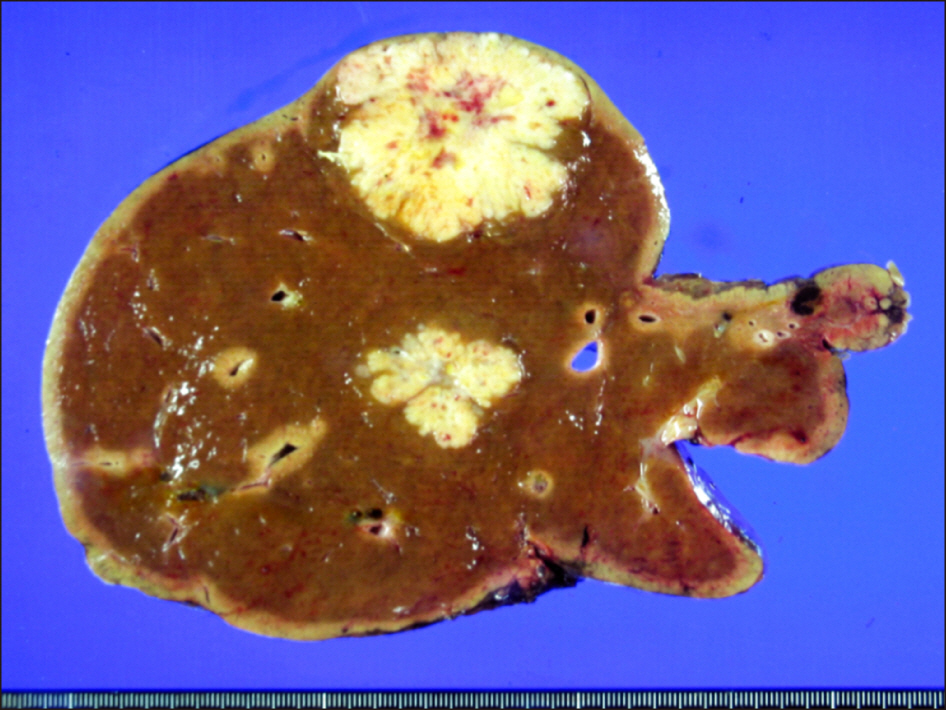

- The feasibility of liver transplantation (LT) for colorectal liver metastasis (CRLM) is still under investigation with only a limited number of LT cases in literature. CRLM is the most common type of liver metastasis, but it was considered as a contraindication to LT for a long time because of poor outcomes. We presented a case of living donor liver transplantation (LDLT) performed in a patient with liver cirrhosis and CRLM. The patient was a 49-year-old female with sigmoid colon cancer and synchronous multiple CRLM. She underwent anterior resection for sigmoid colon cancer and 7 sessions of chemotherapy for CRLM. She suffered from esophageal varix bleeding due to chemotherapy-associated liver cirrhosis. Because of liver cirrhosis and multiple CRLM, the patient underwent LDLT operation using a modified right lobe graft. Serum chorioembryonic antigen level was 220 ng/mL at LT. Explant liver pathology showed multiple metastatic adenocarcinomas of colonic origin, up to 4.7 cm in the greatest dimension. The patient did not receive any specific anti-tumor treatment after LT. She is doing well without any tumor recurrence to date for more than 13 years after the LDLT operation. The experience on our case and literature review suggest that CRLM is not always contraindicated for LT because some selected patients showed improved long-term survival outcomes.